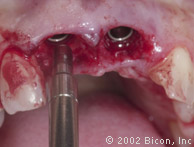

Установка двух 5.0mm x 8.0mm HA имплантантов Bicon

Определение направления оси и глубины шахты имплантантов

Abutment Shoulder Gauge

Вид после установки